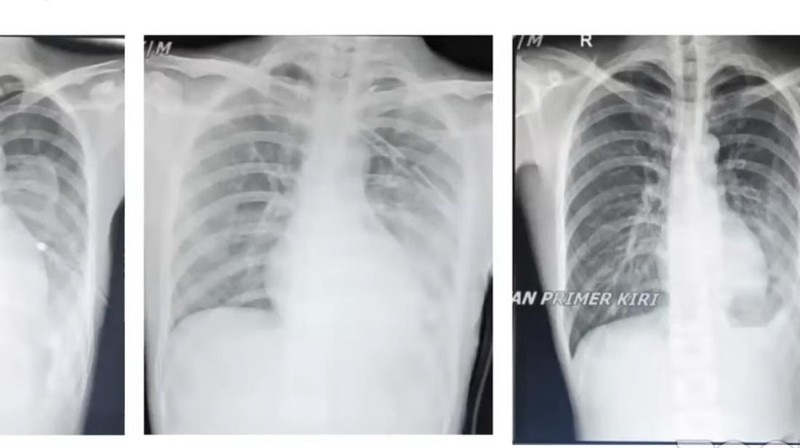

Radang paru dialami oleh bocah 18 tahun asal Indonesia gegara ngevape 3 bulan. (Foto: Tangkapan Layar YouTube Komnas Pengendalian Tembakau)

Penampakan paru-paru remaja usia 17 tahun yang mengonsumsi vape sekaligus merokok. Awalnya mengeluh batuk dan sesak napas. (Foto: Tangkapan Layar YouTube Komnas Pengendalian Tembakau)